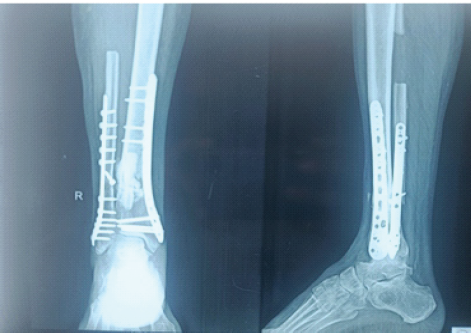

Ipsilateral fibular graft is harvested with its medullary canal reamed to stimulate medullary blood flow. It was contoured into triflanged shape and inserted into the fracture site of tibia. The distal tibial locking compression plate (LCP) was fixed back proximally with new screws. Post-operative period was uneventful. At 3 months follow-up, callus response was observed (Fig. 4). At subsequent follow-ups at 5 months and 9 months, it was observed that the fracture is progressing to union. At 10 months, the fracture united completely (Fig. 5) and the patient was walking without any support (Fig. 6).

Figure 4: Immediate post-operative X-ray after placing fibular strut graft.

Figure 5: One-year follow-up X-ray showing union following fibular grafting.